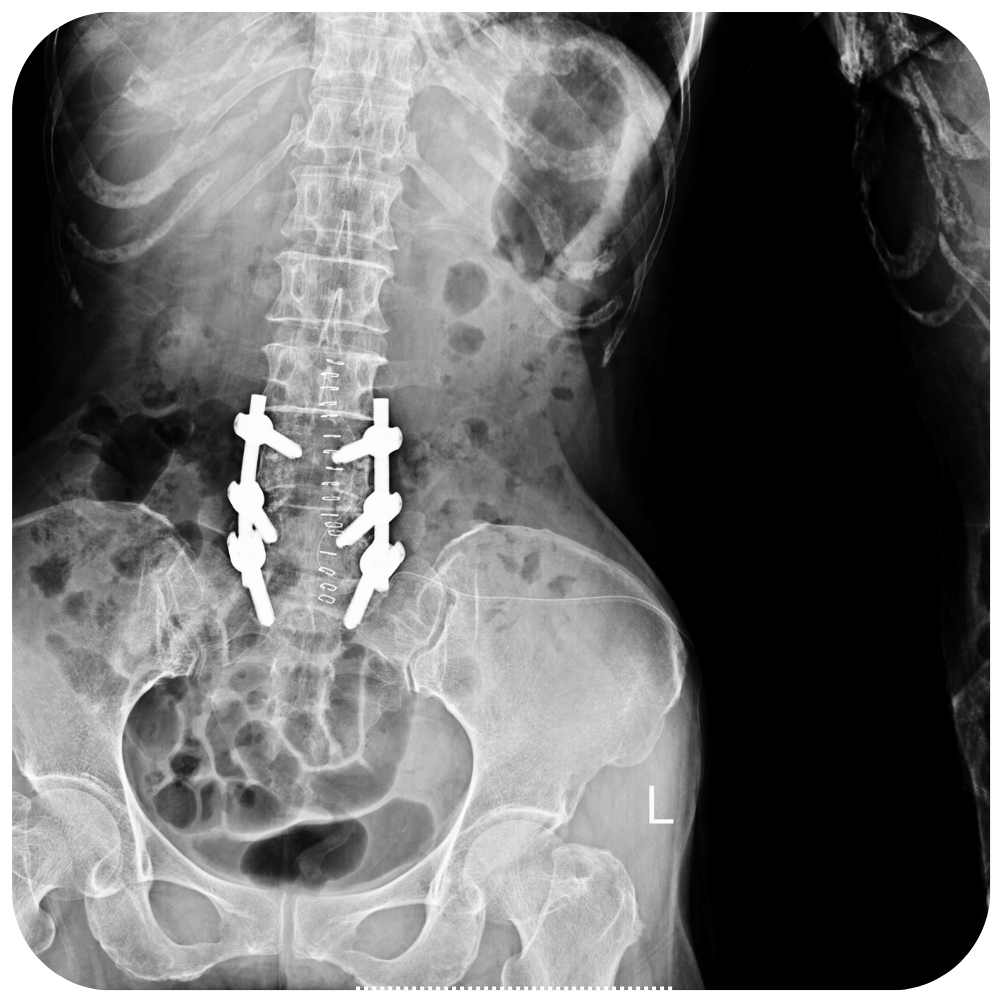

La laminectomía es una cirugía que crea espacio mediante la extracción de la lámina (la parte posterior de la vértebra que cubre el conducto vertebral). También conocida como cirugía de descompresión, la laminectomía agranda el conducto vertebral para aliviar la presión sobre la médula espinal o los nervios.

Debido a que la laminectomía restablece el espacio del conducto vertebral pero no cura la artrosis, es más eficaz para aliviar los síntomas provocados por los nervios comprimidos que para aliviar el dolor de espalda provocado por las articulaciones de la columna.